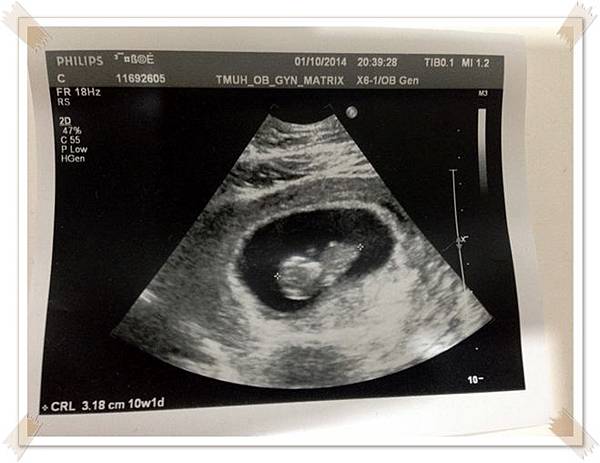

除了懷孕初期有比較常照超音波之外, 從懷孕8週起到28週都是1個月產檢一次

懷孕9週決定之後的產檢就在住家巷口的連鎖婦產科檢查

比起大醫院隨便都要等上2-3小時,一般婦產科看診速度是快多了

但醫療設備一定是比不上大醫院的,,要在大醫院或是一般婦產科產檢就要自行斟酌了